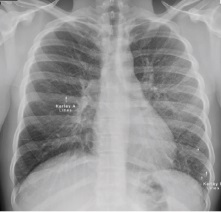

In active pulmonary TB, infiltrates or consolidations and/or cavities are often seen in the upper lungs with or without mediastinal or hilar lymphadenopathy.[1] However, lesions may appear anywhere in the lungs. In HIV and other immunosuppressed persons, any abnormality may indicate TB or the chest X-ray may even appear entirely normal.[1]

Abnormalities on chest radiographs may be suggestive of, but are never diagnostic of, TB.[1] However, if a person has a positive response to the tuberculin skin test and no symptoms of the disease, chest radiographs can be used to rule out the possibility of pulmonary TB.[citation needed]

These are films that are completely normal, with no identifiable cardiothoracic or musculoskeletal abnormality.[citation needed]